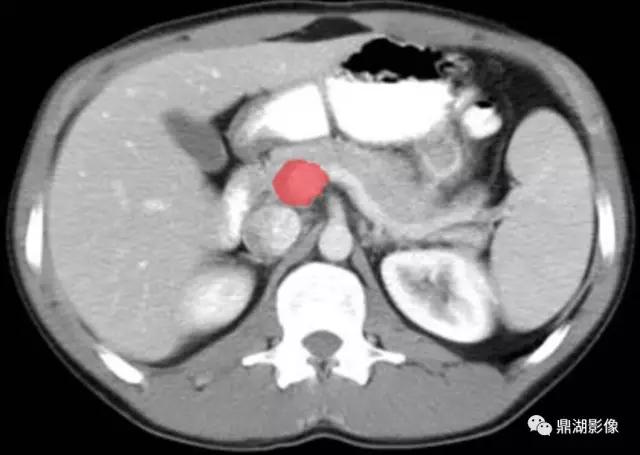

肠系膜上动脉(Superior Mesenteric Artery)

肠系膜上静脉(Superior Mesenteric Vein)